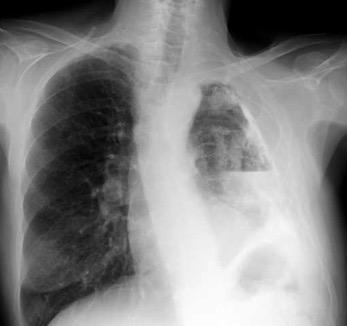

Bilateral………88% ( “< lado izdo.”) Lado derecho…8% Lado izdo.………4%

Trasudados

Muy frecuentes

Fallo cardiaco

Cirrosis hepática

Menos frecuentes

Hipoalbuminemia

Diálisis peritoneal

Hipotiroidismo

Sínd. nefrótico

Estenosis mitral

Raros

Pericarditis constrictiva

Urinotórax

Sind. de Meigs

Causas frecuentes

T. maligno

Derrame metaneumónico

Tuberculosis

TEP

Artritis reumatoide, etc

Asbestos

Pancreatitis

Post-IAM

Post- by-pass coronario

Raras

Drogas

Infección por hongos